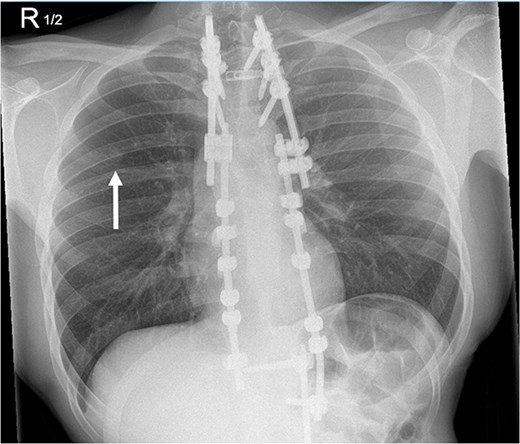

Four days after the surgery, the patient was re-admitted due to fever, cough, and some small-volume purulent discharge from his drain site. A repeat chest radiograph (Fig. 4) was unremarkable, and a wound swab was negative. He was empirically treated with 24 hours of intravenous antibiotics and given a short 4-day course to complete at home. It was felt by the team that a lower threshold for treatment of infection would be appropriate, given his diagnosis of CIP. He was discharged 1 day after re-admission and made a good recovery.

Repeat chest radiograph on re-admission to hospital with fevers and tachycardia.